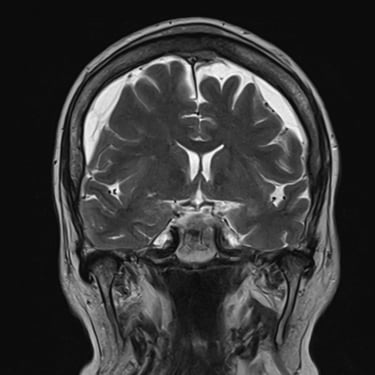

Hematoma Subdural Crónico | Diagnóstico por Resonancia Magnética

El hematoma subdural crónico es una acumulación lenta de sangre entre la duramadre y la superficie cerebral, generalmente secundaria a traumatismos leves en pacientes mayores o anticoagulados. Sus síntomas pueden incluir cefalea persistente, debilidad, alteraciones del lenguaje o cambios en el comportamiento. La resonancia magnética cerebral permite identificar con precisión la extensión y la antigüedad del sangrado, diferenciándolo de otras lesiones intracraneales. Este estudio es esencial para planificar el tratamiento, que puede requerir drenaje quirúrgico mediante trepanación o craneotomía mínima, permitiendo la recuperación neurológica progresiva y reduciendo el riesgo de recurrencia.